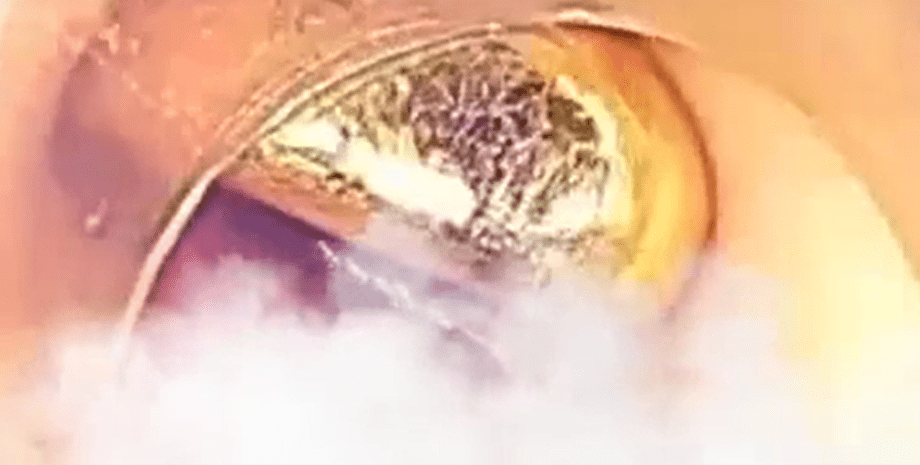

"Мы решили провести инвазивную эндоскопическую процедуру для извлечения золотого слитка из пищеварительного тракта. Операция длилась всего 30 минут и прошла без осложнений. Нам удалось полностью изъять слиток", — рассказали хирурги.